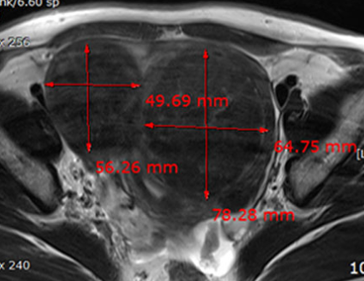

자궁근종 치료 사례

• 시술 전

시술 후